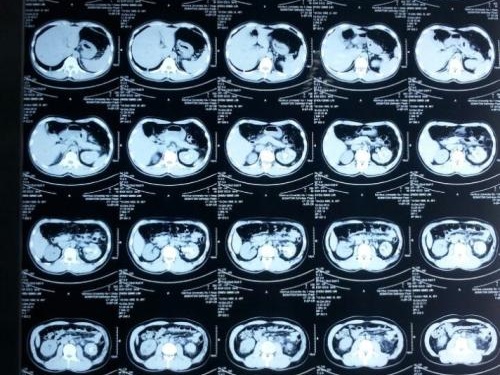

肾结石病是一种常见病。顾名思义,由一些结晶物质组成的有机物质,如草酸和尿酸钙,生长在肾脏上并聚集在肾脏中。大多数情况下是男性。那么为什么有些人会得肾结石呢?来和我一起看看吧。

肾结石处于高湿状态是因为某些因素导致尿液中某些物质的浓度和溶解度降低。从而直接形成结石。这些因素很可能是由尿路感染和异物引起的,也可能是由环境因素、年龄、遗传、种族和饮食习惯引起的。主要原因大概是因为不爱喝水不运动导致体内尿液浓度过高,从而导致结石堆积。也可能是肥胖引起的。肾结石主要是由高脂肪和高胆固醇引起的。一般很多人不吃早餐,容易导致胆酸含量降低。胆汁浓度过高导致胆固醇颗粒增加,从而导致结石。也有可能是体内钙元素过多。其他代谢疾病,如甲状腺功能亢进症,也可能导致肾结石的疾病。